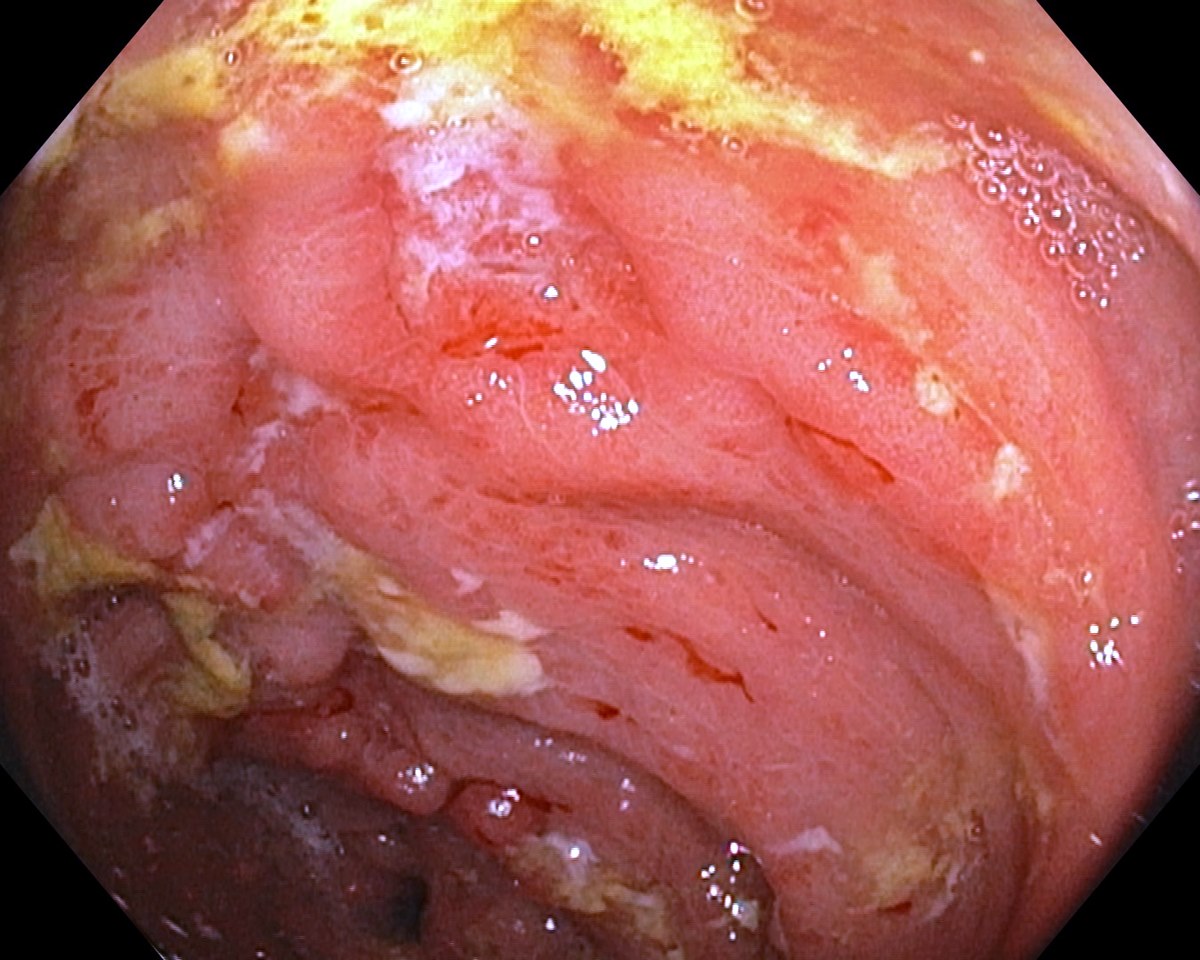

![]() Severe Rectal Crohns Disease  |

Severe Rectal Crohns Disease